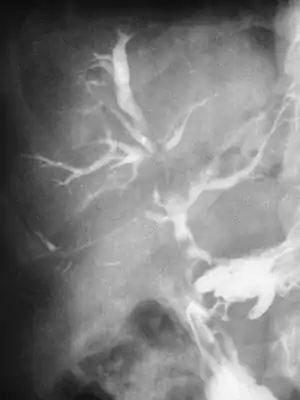

As a radical treatment for portal hypertension, surgical creation of a portacaval fistula produces an anastomosis between the hepatic portal vein and the inferior vena cava across the omental foramen (of Winslow). This spares the portal venous system from high pressure which can cause esophageal varices, caput medusae, and hemorrhoids.